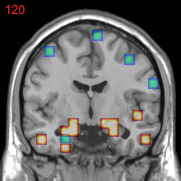

Refer to caption

(f) overlap

Figure 3: Stability of selected voxels across different folds of the cross-validation. The results of 5 different folds are shown in (a)-(e). The voxels with positive β𝛽\beta are in brown, negative ones are in blue. The common/overlapped voxels selected in all 10 folds are shown in green (f). The top row illustrates voxels selected by the lasso model, the mid row illustrates those of GFL and the bottom row shows those of n2superscript𝑛2n^{2}GFL.

Feature Stability. In Figure 3, we show the selected voxels across different folds of CV333Here, parameters were determined by accuracy. Similar results were observed using parameters producing same level of sparsity.. As shown, the selected voxels by lasso vary much across different folds, whereas the selected voxels by GFL are more stable. However, by assuming the positive correlation between the features and the disease labels in n2superscript𝑛2n^{2}GFL, we further increase the stability. To quantitatively evaluate the stability gain, we denote the variables of the k𝑘kth fold of CV as 𝜷(k)𝜷𝑘\boldsymbol{\beta}(k). We introduce two measurements here. In (?), the Estimation Stability (ES) is proposed to measure the stability of the estimation

where ##\# is the number of elements in a set. In Tab. 3, both measurements quantitatively suggest n2superscript𝑛2n^{2}GFL obtains much more stable voxels due to the consideration of the correlation between the features and the disease labels 444We notice that, in (?), the stability is computed using the top 50 positive voxels because these voxels are believe to be the most atrophied ones. By computing the stability of all non-zero voxels, the mDC of GFL drops around 30%percent3030\%. This clearly shows that the instability is caused largely by the undesirable voxels that disagree with the correlation prior (those scattered blue voxels in the mid row)..